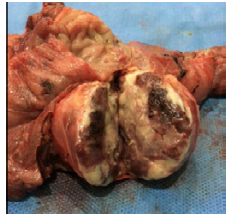

When the mass was released, a giant ulcer was found in the duodenal bulb with abundant clots and 40% involvement of the duodenal wall and marked fibrosis. Additionally, a 4x3x3cm regular, soft and apparently encapsulated mass was found on the head of the pancreas; immersed in pancreatic tissue and with foci of hemorrhage when cut (Figure 2).